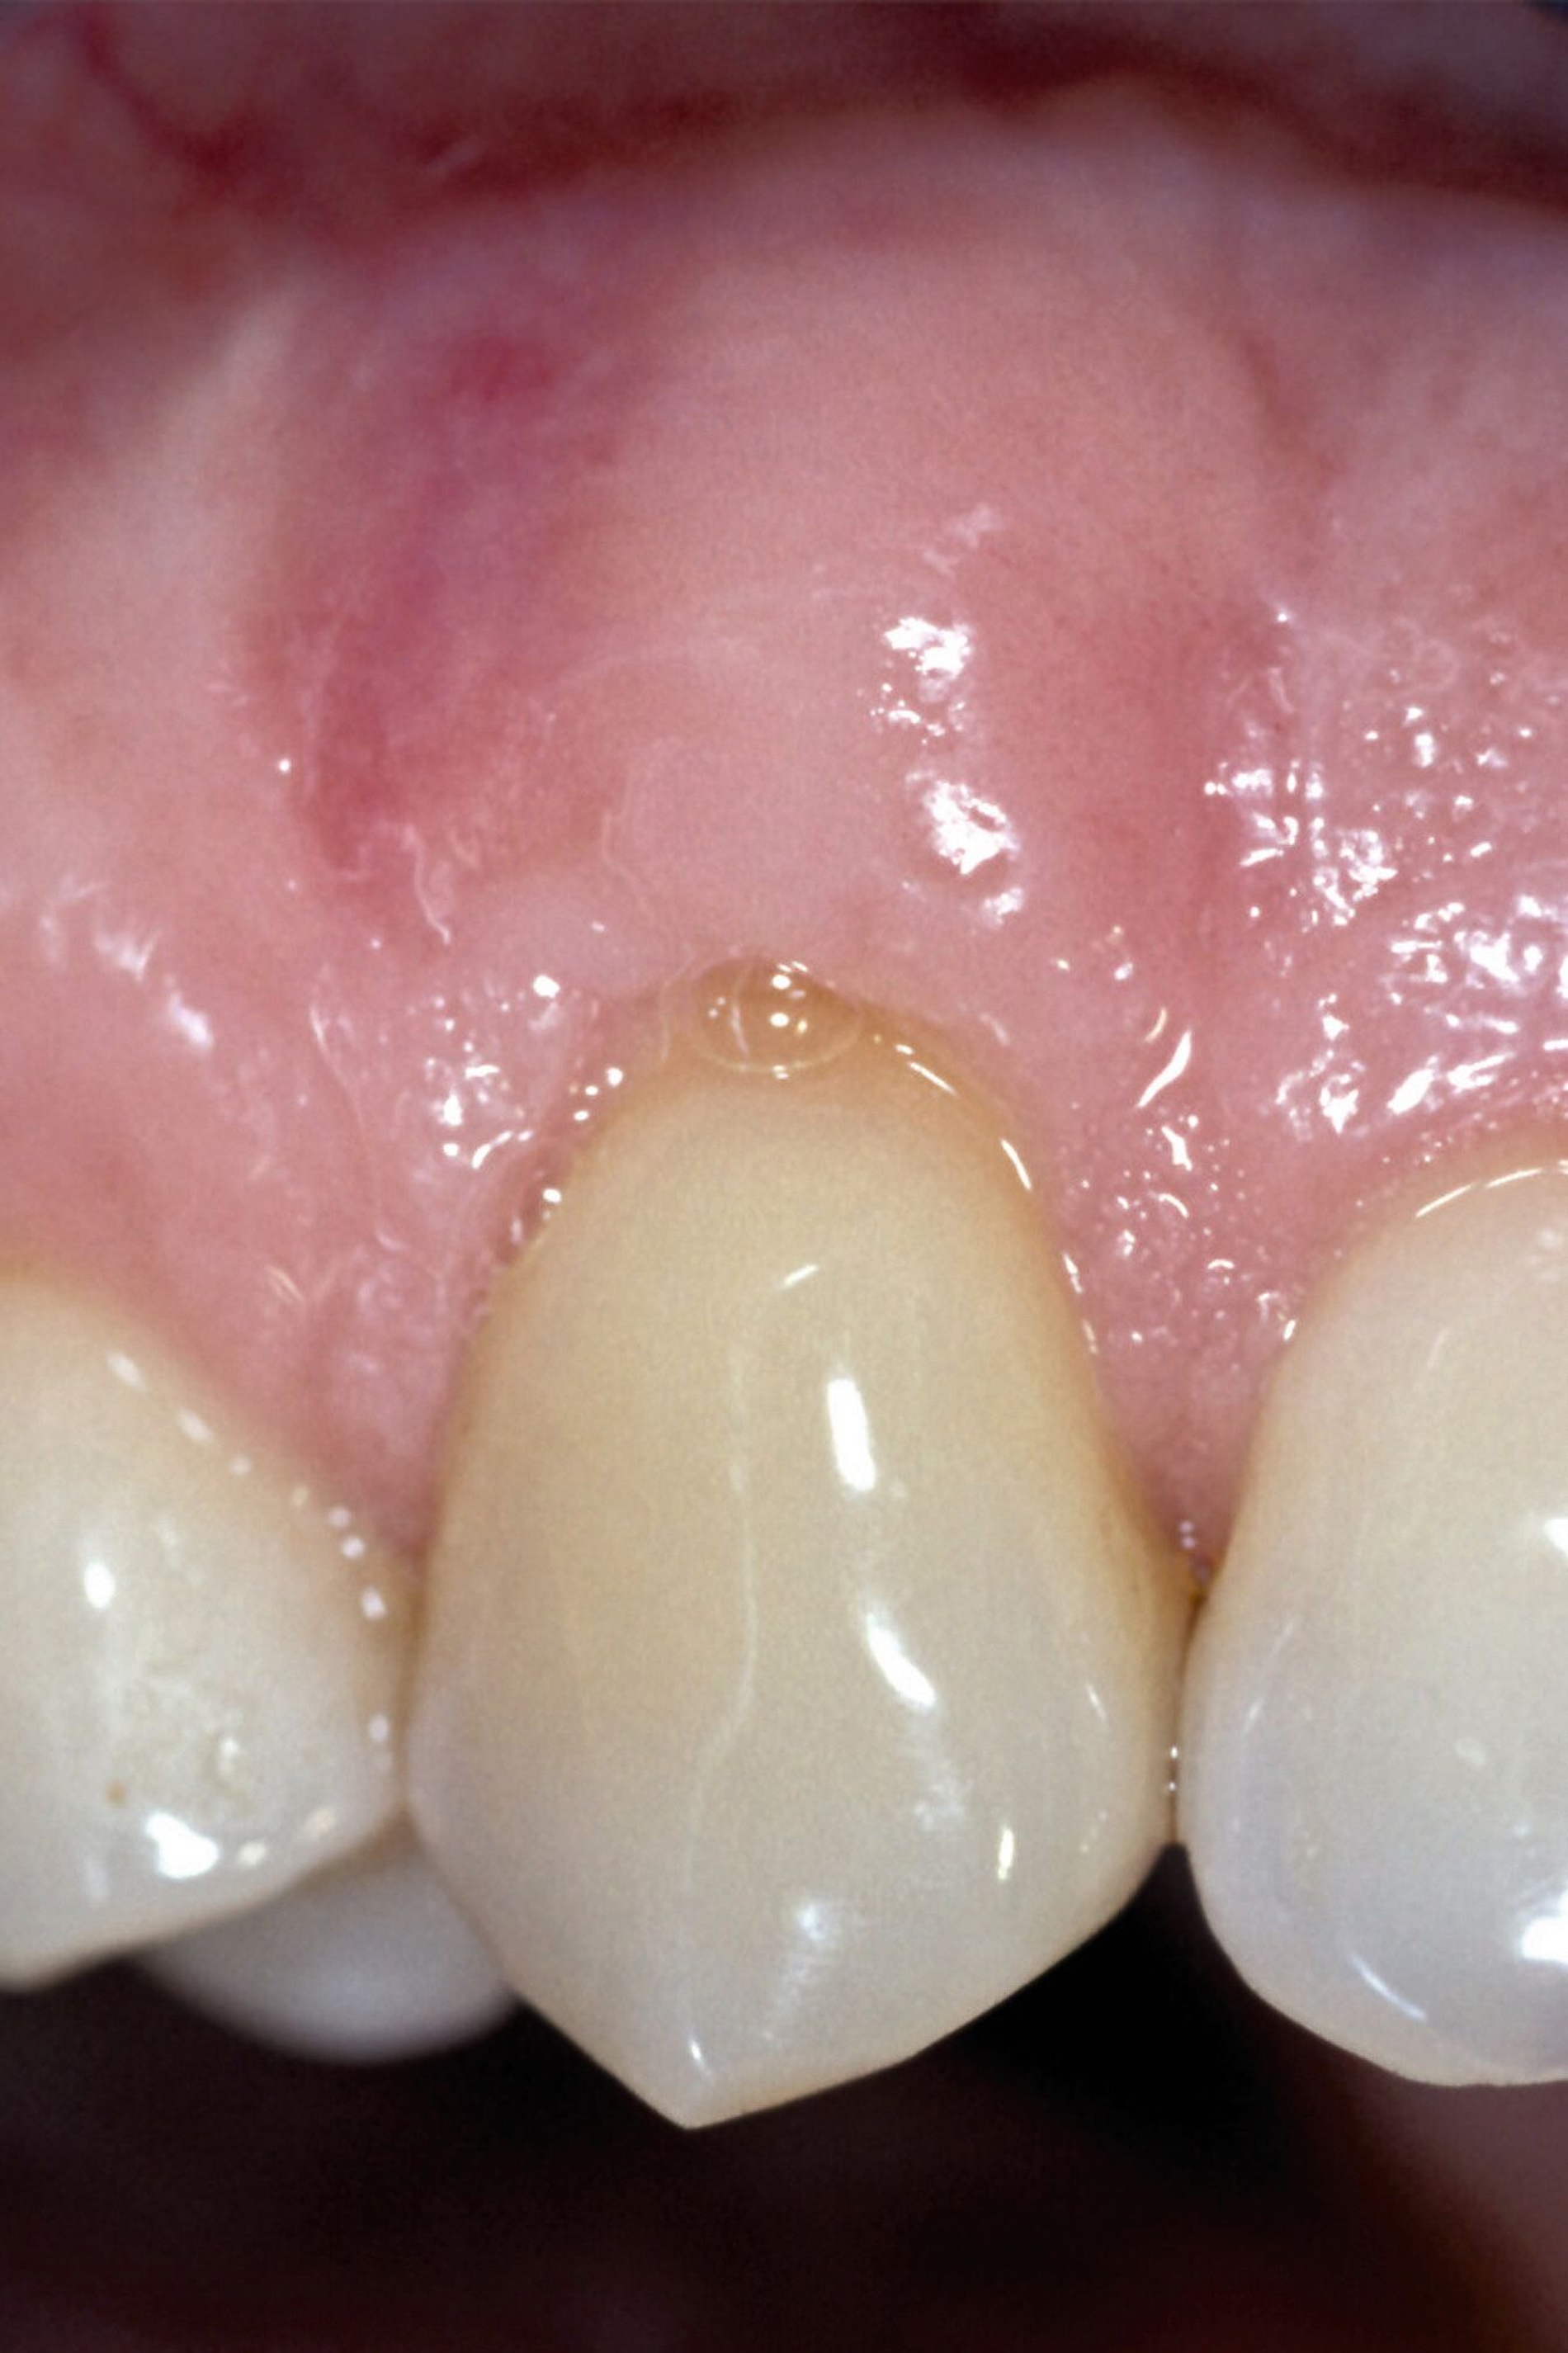

Tunkel et al. versuchten die Vorteile von Zucchellis Koronalem Verschiebelappen und Sculeans Lateral Geschlossenem Tunnel in einer Technik zu vereinen: dem Lateral Geschlossenen Koronalen Verschiebelappen (LCAF) [Tunkel et al., 2024] (Abbildung 3). Bei dieser Methode, mit der vor allem tiefe singuläre parodontale Rezessionen behandelt werden, wird die Koronalverschiebung ohne Entlastungsinzisionen kombiniert mit dem lateralen Verschluss der tiefen parodontalen Rezession.

Das Vorgehen ist hier wie folgt: Zunächst wird im Bereich der tiefen Rezession der Gingivarand geringfügig exzidiert, um ein Zusammenwachsen der geschlossenen Lappenanteile zu ermöglichen. Anschließend wird der Schnitt in horizontaler Richtung durch leicht bogenförmige Schnittführungen auf Höhe der Schmelz-Zement-Grenze erweitert, um mindestens zwei Zähne rechts und links von der Rezession (Abbildung 3b). Im Unterkiefer-Frontzahnbereich, wo die Rezessionen heutzutage am häufigsten vorkommen, sollte der Lappen mindestens von Eckzahn zu Eckzahn gebildet werden, um ein harmonisches Ergebnis nach Abheilung zu erreichen. Auf vertikale Entlastungsinzisionen kann komplett verzichtet werden. Anschließend erfolgt die Lappenpräparation nach dem bereits für koronale Verschiebelappen gängigen Prinzip teilschichtig-vollschichtig-teilschichtig.

Die Papillenbereiche werden mit dem Skalpell scharf vom Periost abgelöst. Dann wird das Periost durchtrennt und bis zur mukogingivalen Grenze ein vollschichtiger Lappen gebildet. Nach Überschreiten dieser wird wieder zweischichtig präpariert. Hierdurch wird eine gute Mobilisation des Lappens erreicht, die eine ausreichende Koronalverschiebung ermöglicht. Entgegen dem in früheren Jahren propagierten komplett teilschichtigen Vorgehen, kann durch dieses Verfahren die Gefahr von Lappenperforationen signifikant gesenkt werden, da diese insbesondere im Bereich der mukogingivalen Grenze auftreten. Nachdem die Lappenareale mesial und distal der Rezession gelöst sind, können diese durch zwei bis drei feine monofile Nähte miteinander verbunden werden (Abbildung 3c). Sobald durch diese Naht ein zusammenhängender koronaler Verschiebelappen entstanden ist, werden die Papillenbereiche koronal des gebildeten Lappens entepithelialisiert. Nach Entnahme eines Bindegewebstransplantats oder entepithelialisierten freien Schleimhauttransplantats wird die Wurzeloberfläche mit EDTA-Gel konditioniert und anschließend werden Schmelz-Matrix-Proteine aufgetragen (Abbildung 3d). Diese bewirken die Bildung eines new attachment und fördern zudem die Wundheilung, was gerade bei den delikaten lateralen Verschiebelappen von Vorteil sein sollte [McGuire und Cochran, 2003; Almqvist et al., 2011; Thoma et al., 2011; McGuire et al., 2016]. Anschließend wird das Transplantat durch Nähte ausgehend vom oralen Papillenbereich fixiert (Abbildung 3e). Zuletzt wird der Lappen mit sogenannten doppelten Umschlingungsnähten im Bereich der Papille durch Zug nach koronal und oral fixiert, was eine perfekte Positionierung ermöglicht [Zuhr et al., 2009] (Abbildung 3f). Hierbei muss darauf geachtet werden, dass der Lappen die Schmelz-Zement-Grenze um mindestens 2 mm überdeckt, um eine hundertprozentige Wurzeldeckung erwartbar zu machen [Pini Prato et al., 2005].

Der Lateral Geschlossene Koronal Verschobene Lappen ermöglicht eine annähernd narbenfreie Deckung singulärer parodontaler Rezessionen durch Verzicht auf vertikale Entlastungsinzisionen (Abbildung 3g). Das Lösen der Papillen im Rahmen der Verschiebung ermöglicht eine deutliche Anhebung des Lappens und somit durch großzügige Überdeckung das Erreichen vollständiger Wurzeldeckungen. Durch den lateralen Verschluss im Rahmen der tiefen, über die mukogingivale Grenze hinausgehenden Rezession kann keratinisierte Gingiva im Bereich dieser hergestellt und eine übermäßige Mobilisation und damit Einschränkung des Vestibulums verhindert werden.